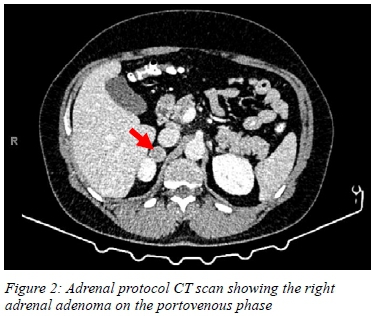

Adrenal protocol contrast CT scan showed a right adrenal mass measuring 21.8 x 21.0 x 21.8 mm in size with a radio-density of 95.9 HU on the portovenous phase. The mass had an absolute washout of 80.5% and a relative washout of 55.8% in keeping with an adrenal adenoma. Aside from the adrenal adenoma, the right adrenal gland had normal morphology and parenchymal enhancement. The left adrenal gland was normal in size with no evidence of cysts or masses. The limbs of both adrenal glands were not enlarged, lowering suspicions of bilateral adrenal hyperplasia.